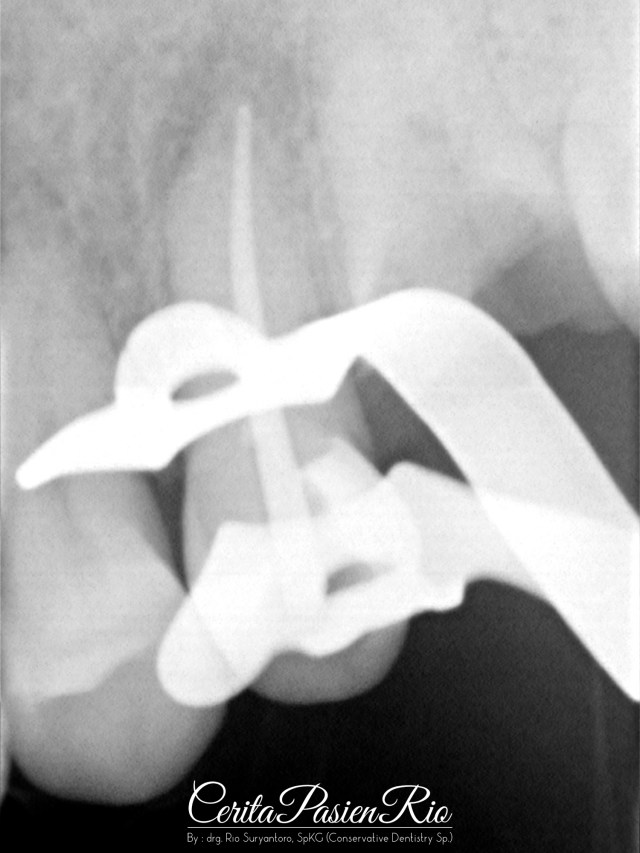

gambar 6. pemasangan rubber dam pada gigi 14, 15, dan 16. memeriksa isolasi yang baik sebelum pembuatan dinding distal.